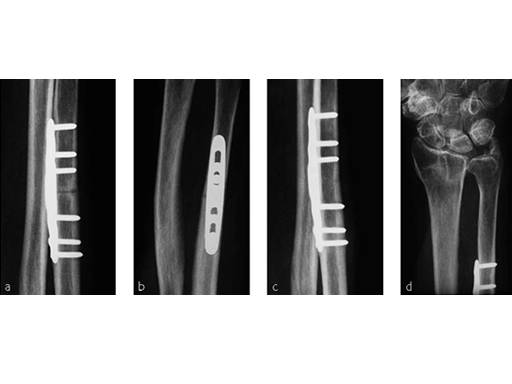

Case 1: Distal radius fracture

A 69-year-old female patient had suffered a right distal radius fracture one year earlier, and received conservative management. Symptoms included pain and impaired function about the wrist and forearm, with decreased forearm rotation. Painful DRUJ (DASH: 34, PWRE: 29).